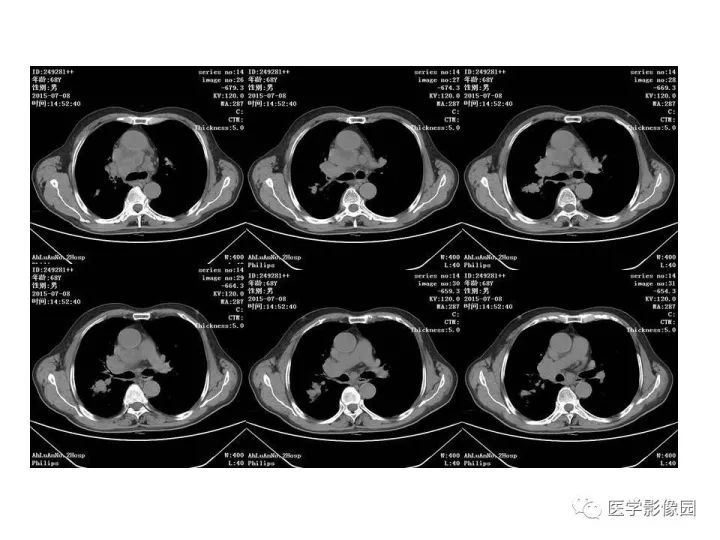

【病例】右肺上叶小细胞癌1例CT影像表现

【病例】右肺上叶小细胞性肺癌1例CT影像表现